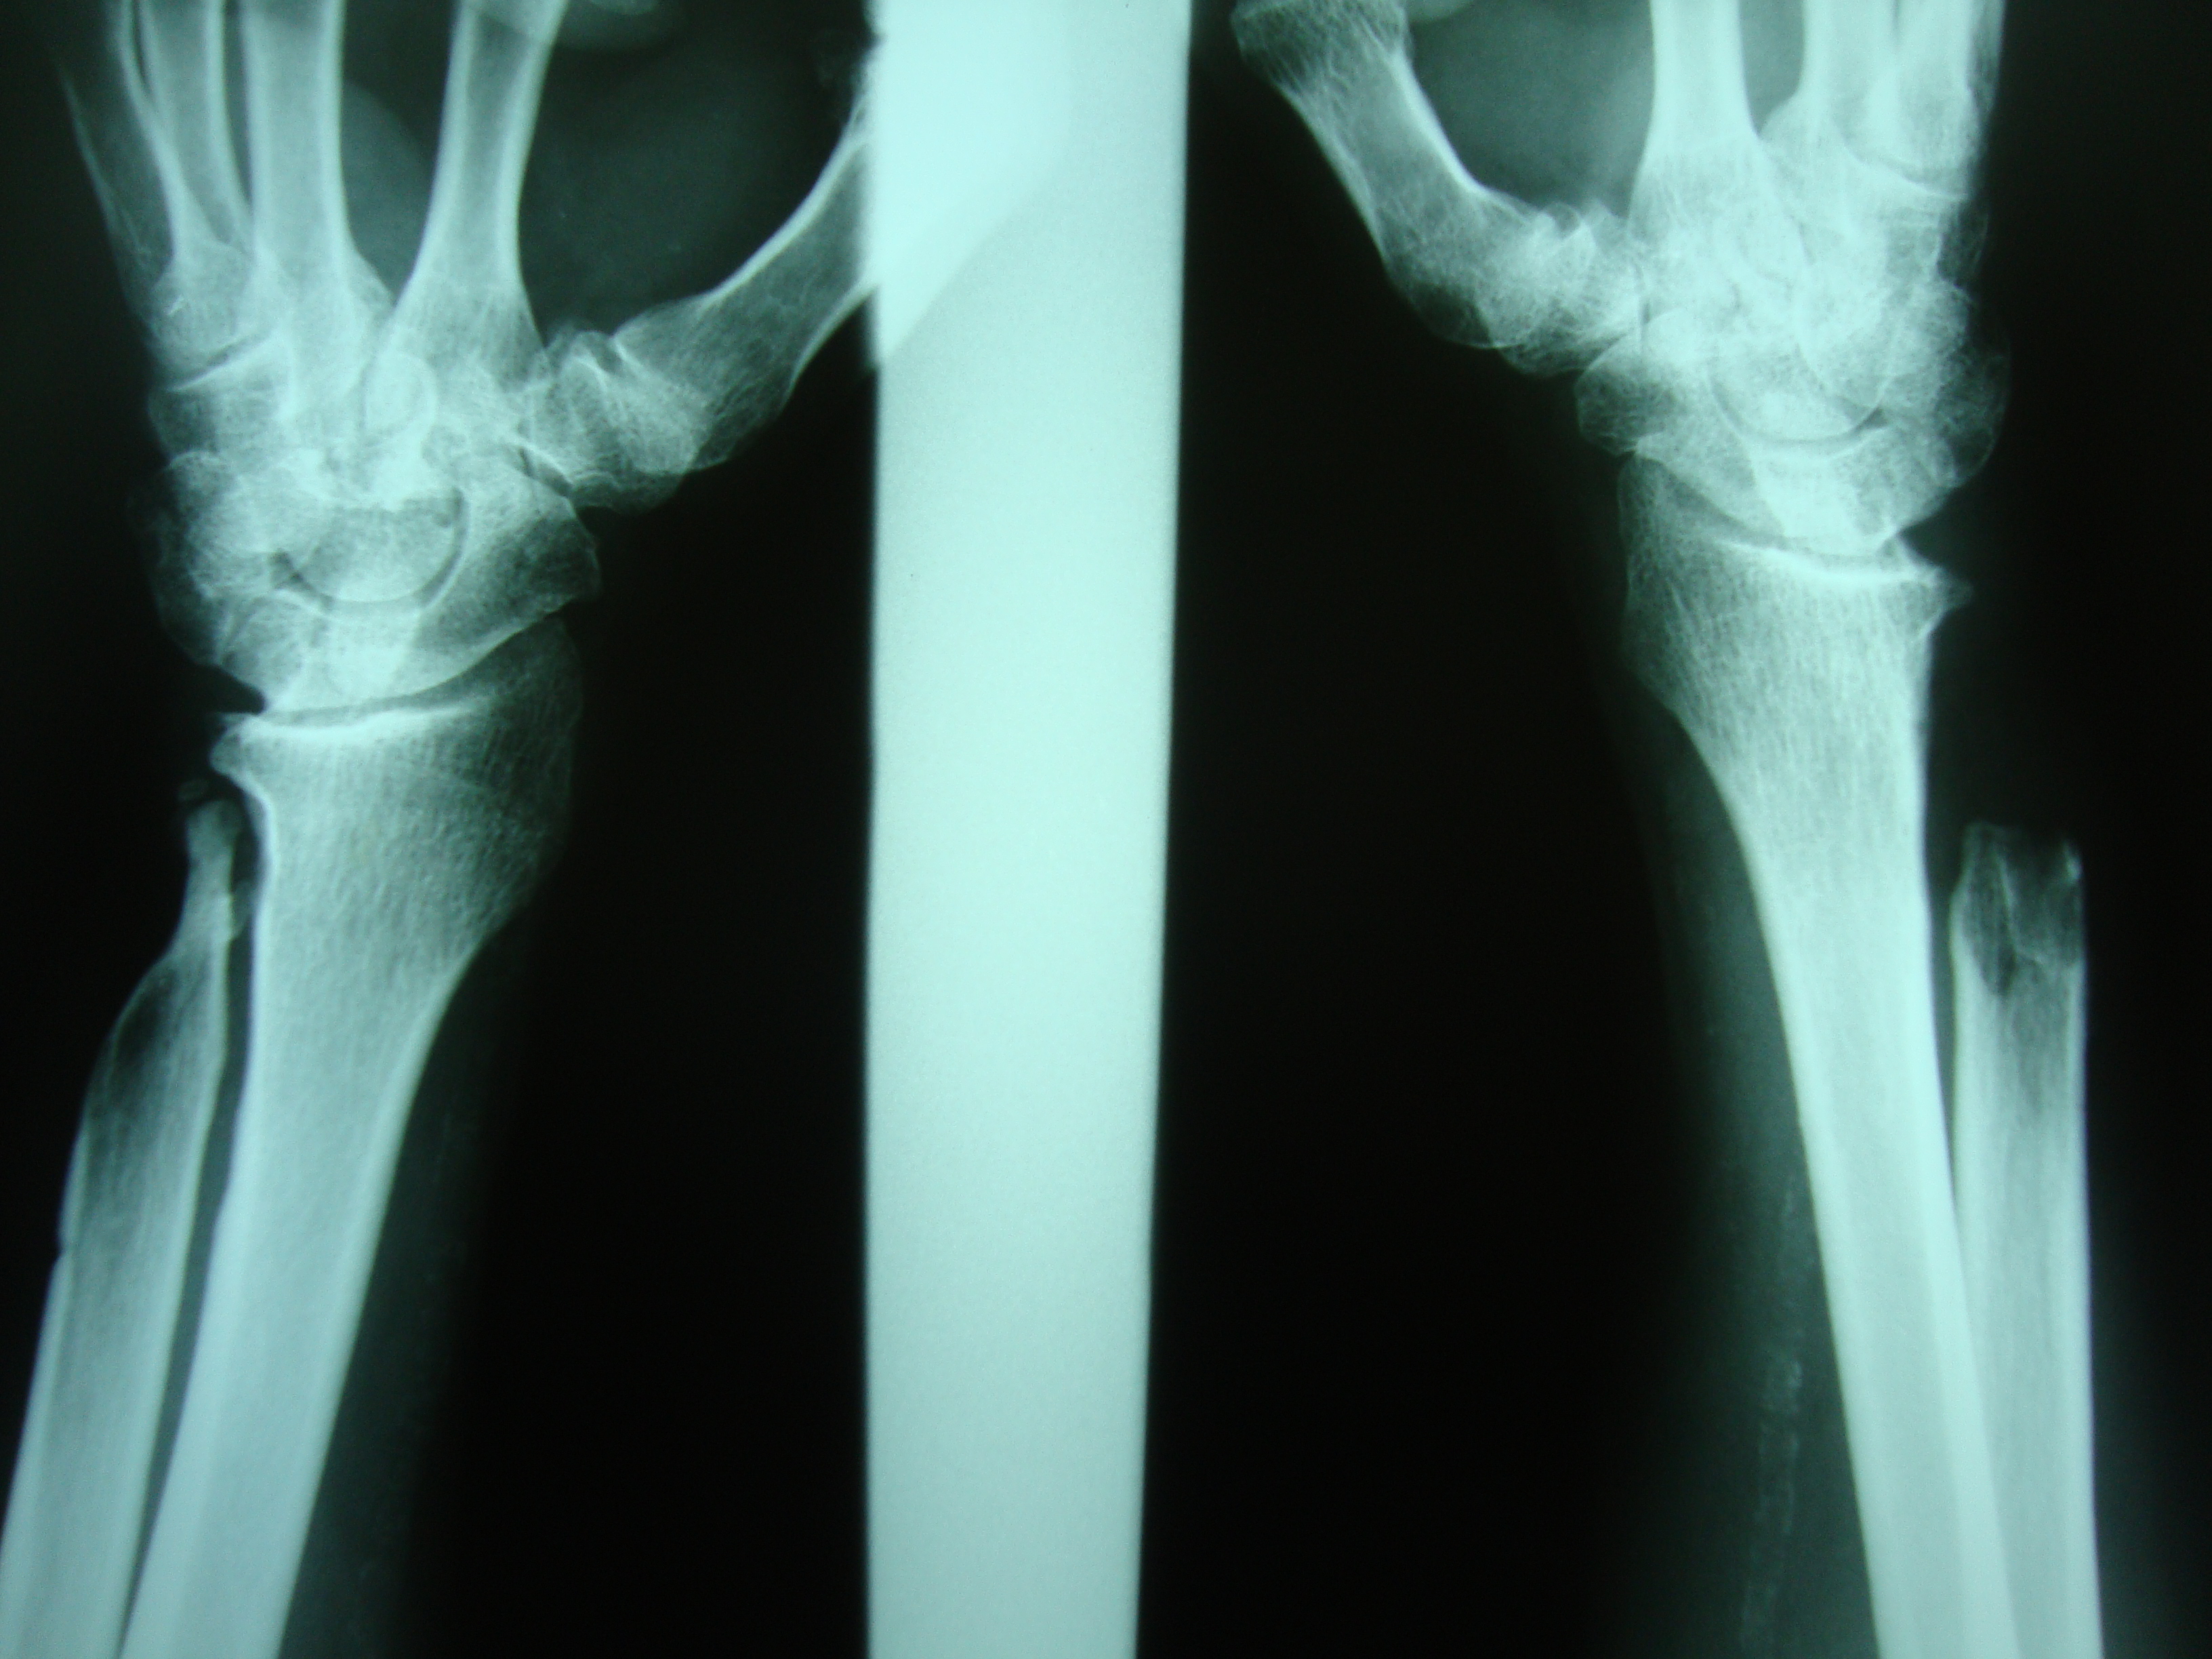

Rotura de los tendones extensores de los dedos por cúbito plus idiopático bilateral. Informe de un caso.